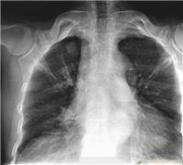

• 肺腫瘤

肺腫瘤又叫支氣管肺癌(Lung.Carcinoma)是常見的惡性腫瘤之一,近數(shù)十年肺癌的發(fā)病率和死亡率都有明顯增高的趨勢(shì)。肺癌的早期診斷是提高治療效果的有效途徑,影像學(xué)和痰液脫...